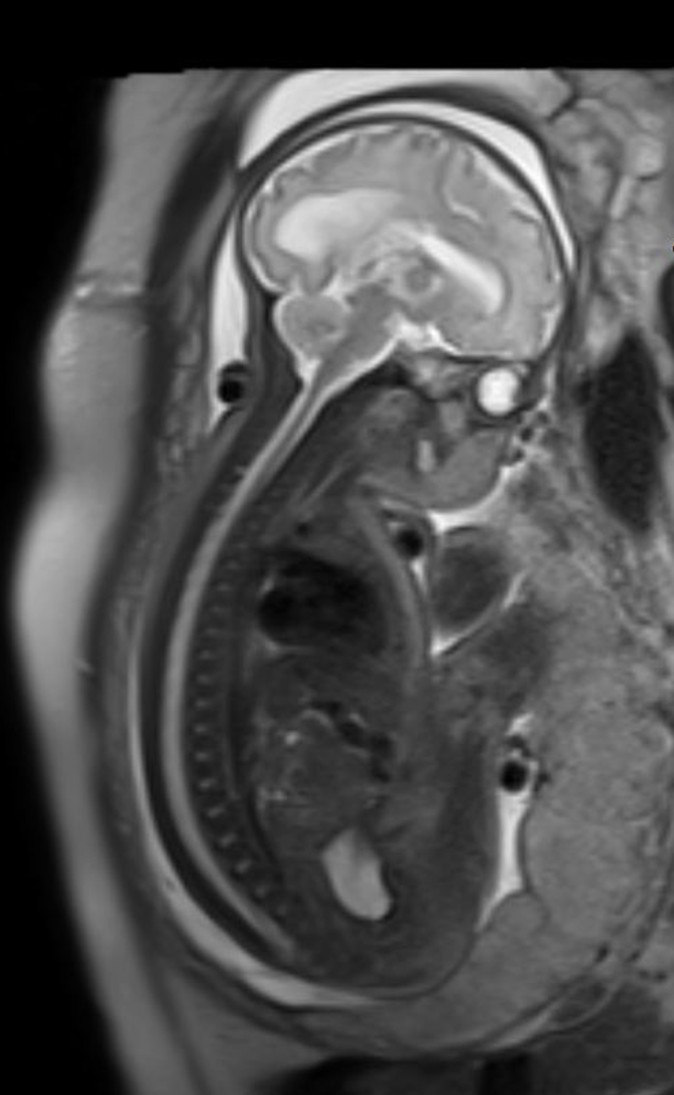

Das fetale MRT (Magnetresonanztomographie) ist ein strahlungsfreies Verfahren, mit dem wir Organe und Strukturen Ihres ungeborenen Kindes besonders detailreich darstellen. Es ergänzt die pränatale Ultraschall-Diagnostik und hilft, Fragestellungen präzise zu klären und die weitere Betreuung zu planen.

- Abklärung von Auffälligkeiten im Ultraschall, z. B. Gehirn, Wirbelsäule, Lunge, Bauchorgane

- Beurteilung von Organreife und Entwicklung, wenn die Sicht im Ultraschall eingeschränkt ist (z. B. mütterlicher Body-Mass-Index, Lage des Kindes)

Unsere Neuroradiologen arbeiten eng mit Pränatalmedizinern, Neonatologen, Pädiatern und Chirurgen zusammen. Modernste Geräte und spezialisierte Protokolle sorgen für hohe Bildqualität – auch bei kindlichen Bewegungen.